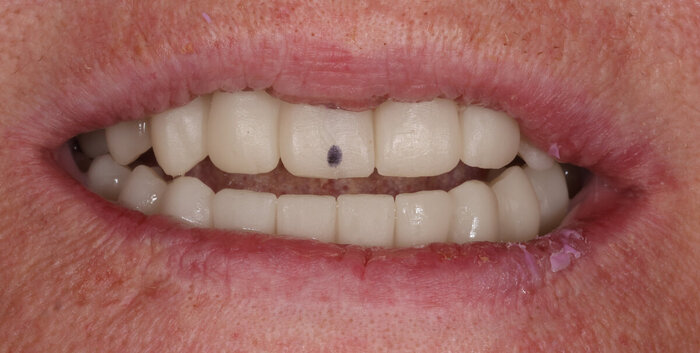

Зубы:

Протезы

Получилось так, что сверху всего 8 зубов, по 4 с каждой стороны. Чёрная точка (которую вы точно увидите, скос эмали на зубе 1.1) - конструктивные особенности, всё это будет закрыто пломбировочным материалом. Зуб 1.1 - дополнительный имлантат, который потом планируем убрать. Он нужен лишь для усиления, ибо торк полноценный был получен только на одном из остальных 6-ти установленных.

Теперь посмотрим, как это выглядит во рту:

2 недели после тотальной работы на имплантатах - 2 челюсти

Шахты имплантатов закрыты временным материалом на 2 дня, он не очень эстетичный по цвету.